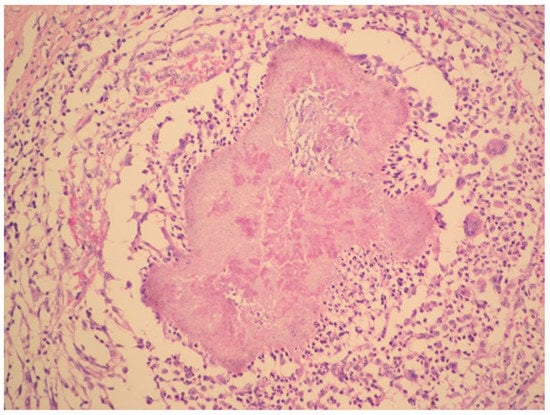

The diagnosis of metastatic ovarian cancer was assumed. Histology of a CT-guided fine-needle liver biopsy sample revealed fibroproliferative inflammation and chronic abscess with actinomycotic granules.

The radical surgery was postponed for two months until the patient´s nutritional status improved. Hysterectomy, bilateral salpingo-oophorectomy, appendectomy and adhesiolysis was performed. On the cut, the mass on the right ovary, with dimensions of 50 × 50 × 30 mm, showed yellowish tissue with necrosis. Histopathology showed that the mass consisted of confluent granulomas with purulent exudate containing fibrillar structures corresponding to actinomycotic granules despite two months of targeted antibiotic treatment (Figure 3).

Figure 3. Histopathology shows granuloma with purulent exudate and actinomycotic granules. Haematoxylin–eosin stain. (With kind permission of Dr. Kamila Benková, Department of Pathology, Hospital Na Bulovce.).